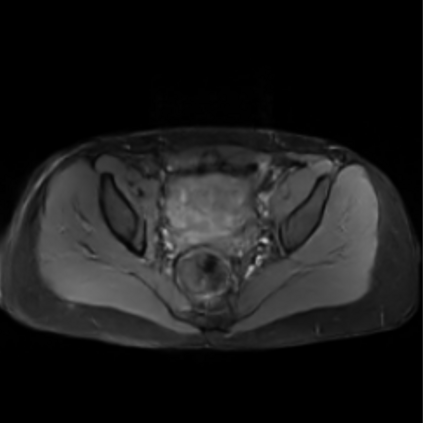

Motion artifacts are a primary source of magnetic resonance (MR) image quality deterioration with strong repercussions on diagnostic performance. Currently, MR motion correction is carried out either prospectively, with the help of motion tracking systems, or retrospectively by mainly utilizing computationally expensive iterative algorithms. In this paper, we utilize a novel adversarial framework, titled MedGAN, for the joint retrospective correction of rigid and non-rigid motion artifacts in different body regions and without the need for a reference image. MedGAN utilizes a unique combination of non-adversarial losses and a novel generator architecture to capture the textures and fine-detailed structures of the desired artifacts-free MR images. Quantitative and qualitative comparisons with other adversarial techniques have illustrated the proposed model's superior performance.

翻译:移动文物是磁共振(MR)图像质量恶化的一个主要来源,对诊断性能产生强烈影响。目前,MR运动的校正要么是预期性的,借助运动跟踪系统,要么是追溯性的,主要是利用成本昂贵的计算迭代算法。在本文中,我们使用名为MedGAN的新颖的对抗性框架,联合追溯性地校正不同身体区域的硬性和非硬性运动文物,而不需要参考图像。 MedGAN利用非对抗性损失和新型生成器结构的独特组合来捕捉无MR图象的纹理和精细详细结构。 与其他对抗性技术的定量和定性比较展示了拟议模型的优异性表现。